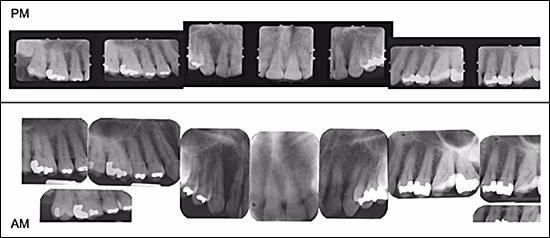

Teeth have the ability to survive decomposition and withstand extreme temperature changes, which is why dental evidence comparison is one of the most dependable and reliable methods of identification4 This is made possible by comparing features of an unknown individual (post-mortem dental records) with a known individual (ante-mortem dental records). For this reason, it is extremely important an accurate and detailed evaluation of the unknown individual is documented to provide the best possibility of successful comparison with ante-mortem records.4 The following is collected for post-mortem documentation: photographs (digital or film based) which provide the ability to view specific features without having to review the body, radiographs (full mouth series) (Figure 1), and a complete dental record for post-mortem and ante-mortem paperwork (Figures 2A & 2B).17 The primary goal of post-mortem dental records is to locate, identify and document anatomical structures, dental restorations and dental appliances that will assist in the comparison process.4 The more information documented from the post-mortem examination, the better the possibility for successful comparison.4

Figure 1. Comparison of Post-mortem (PM) with Ante-mortem (AM) Radiographs.

Source: Dr. McCunniff.